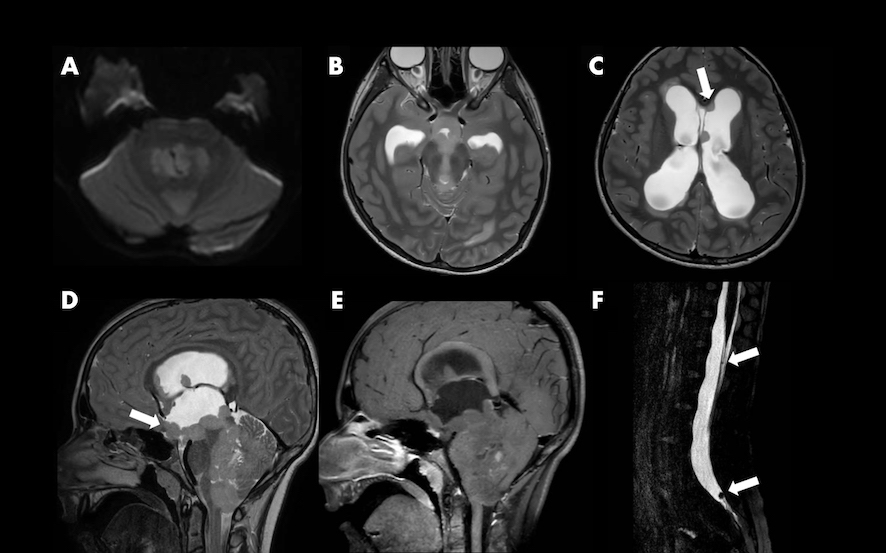

Veniva eseguita una risonanza magnetica cerebrale con evidenza di una voluminosa massa disseminata con coinvolgimento del quarto ventricolo, dell’acquedotto mesencefalico e con diffusione del liquido cerebrospinale lungo i ventricoli laterali e il midollo spinale con conseguente idrocefalo scompensato e ipertensione intracranica (Figura).